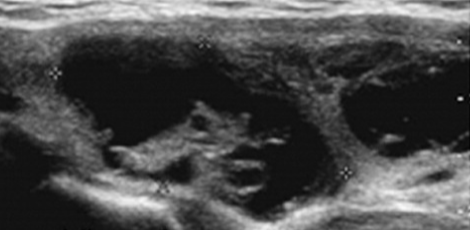

교수님은 지금까지 만났었던 의사들과 다르게 초음파 영상을 환자와 함께 바라보면서 암의 상태에 대하여 자세히 설명해 주셨다. 지금까지 환자에게 보여주며 설명해 준 의사는 단 한 명도 없었다.

그렇게 설명을 이어가던 교수님은 한참을 모니터를 응시다가 고개를 갸우뚱하시면서, "0.9가 아니고. 0.7 이네요." 하는 게 아닌가. 비전무가인 내가 봐도 0.7로 보였다. 한 달도 안 되어서 0.2가 작아진 건 아닐 것이고, 교수님도 수술에 대한 결정권은 환자에게 있다고 했다.

암이라는 사실은 변함없지만, 의사들은 갑상선암을 절제하는 수술 생각만 앞섰지 악성 암 조직의 사이즈를 다시 측정해볼 생각도 안 했던 것이었다. 그렇지 않고서야 그 많은 의사들 모두가 0.9cm라는 일관된 사이즈로 측정한 걸까? 로또 1등 확률만큼이나, 어려운 가능성이라고 본다. 유일하게 내 눈앞에서 길이를 함께 측정했었던 교수님의 진단이 정확하다고 본다.

따라서 이전까지 진료했었던 대학교병원 의사들은 서류상에 적힌 '0.9cm'만 믿고 측정을 안했다고 보여진다. 의료업계 종사자가 아닌 일반인도 기본적인 초음파상 사이즈 측정법은 잘 알 거다. 특히 임산부 태아 초음파검사를 받아보거나 옆에서 지켜본 경험이 있다면 잘 알거다. 초음파 영상자료 모니터 상에서 클릭 두 번이면 길이가 측정된다. 이처럼 초음파영상자료를 판독하는 프로그램에서 사이즈 크기 측정법은 간단하다.